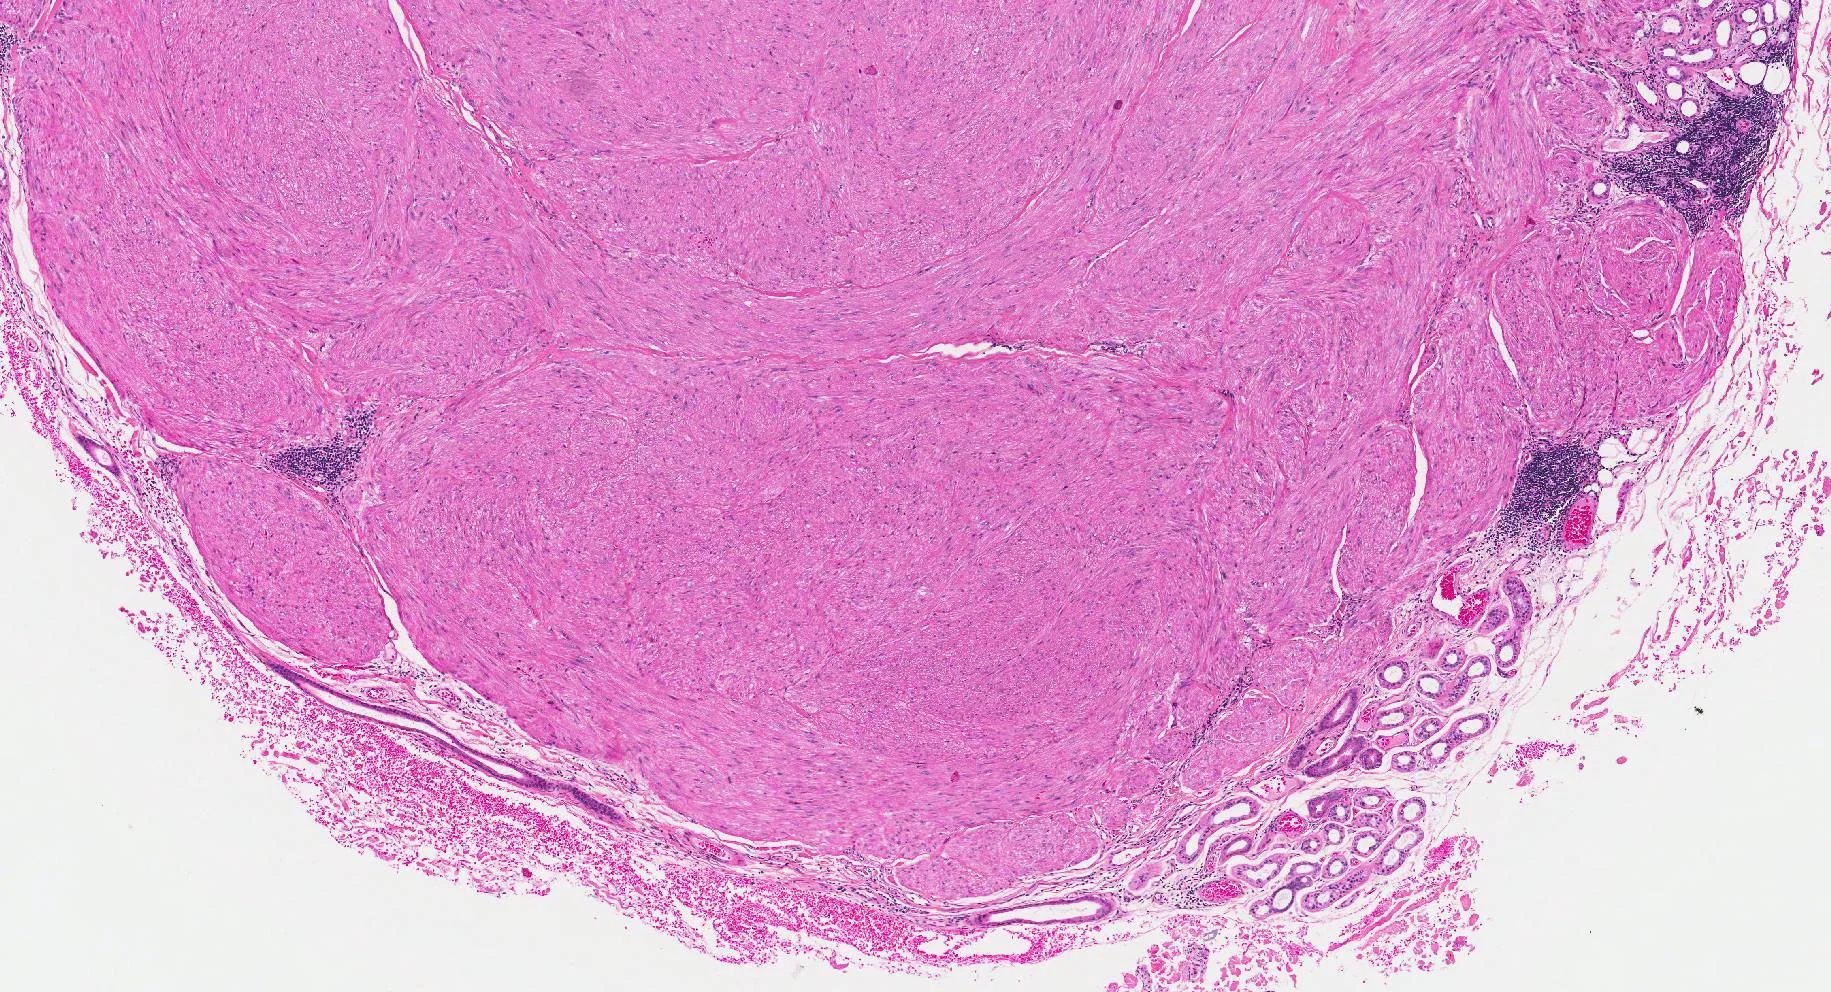

Painful nodule arm, male 41. History of previous similar nodules.